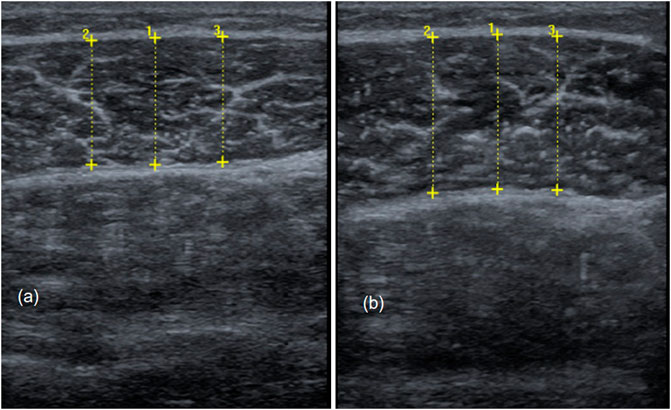

Figure 7 shows examples of sonography measurements from pre to posttest of the control leg and the intervened leg.

FIGURE 7. Comparison of muscle thickness from pre-to posttest in the non-stretched control leg (A) and the intervened leg (B).

Two-way ANOVA demonstrated high effects for the time dependent effect (ƞ2 = 0.545) and for the time × group interaction (ƞ2 = 0.406).

Measures of skeletal muscle architecture were done using two-dimensional B-mode ultrasound (Mindray Diagnostic Ultrasound System). Here, muscle thickness represents the most employed measure of muscle dimension (Sarto et al., 2021) according to its correlation to muscle cross-sectional area, which is proportional to the number of parallel sarcomeres, thereby influencing maximal force production (Lieber & Fridén, 2000; Narici et al., 2016; May et al., 2021). In our examination, ultrasound images from the lateral gastrocnemius were recorded using a linear transducer with a standardized frequency of 12–13 MHz. Each participant was placed prone on a table with the feet hanging down at the end to ensure no contraction in the calf muscles. Then, the sonographer identified the proximal and distal landmark of the lateral gastrocnemius for each participant and measurement (Perkisas et al., 1999). The transducer was placed at 30% of the distance from the most lateral point of the articular cleft of the knee to the most lateral top of the lateral malleolus (see Figure 3) (Perkisas et al., 1999). For measuring muscle thickness, the transducer was positioned at the midpoint of the muscle belly perpendicular to the long axis of the leg (Sarto et al., 2021). The muscle belly was determined as the center of the muscle between its medial and lateral borders. This is the point where the muscle’s anatomical cross-sectional area is maximal (Fukunaga et al., 1992). In addition, the image plane is best aligned with the muscle’s fascicles, including minimal fascicle curvature (Bénard et al., 2009; May et al., 2021; Raj et al., 2012). Before starting the measurement, transmission gel was applied to improve acoustic coupling and to reduce the transducer pressure on the skin. Then, the sonographer ensured that the superficial and deep aponeuroses were as parallel as possible by holding and thereby rotating the transducer around the sagittal-transverse axis to the determined point on the skin without compressing the muscle. Hence, the visibility of the fascicles as continuous striations from one aponeurosis to the other was optimized. Muscle thickness is defined as the linear, perpendicular distance between the two linear borders of the skeletal muscle and was obtained by averaging three measurements across the proximal, central, and distal portions of the acquired ultrasound images (Franchi et al., 2017; Sarto et al., 2021). Two persons independently evaluated muscle thickness using the image processing software GIMP 2.10.28. The objectivity of the evaluators was found to be between 0.85 (control leg) and 0.94 (intervention leg).

In this work, a significant improvement in maximal strength in the calf muscles was achieved by daily one-hour stretching training. There was a significant improvement in maximal isometric strength production determined in the extended knee joint by approximately 16.8% from 1478.4 ± 309.7N in pretest to 1726.8 ± 315.8N in the stretched leg. In comparison, an average maximal strength increase of 1.4% from 1542.3 ± 339.1N to 1564.5 ± 300.5N was determined in the non-stretched control leg while no significant increase was determined between legs of CG. Furthermore, we determined enhanced maximal dynamic strength via 1RM testing by 25.1% and 11.4% from 91.9 ± 35 kg to 115 ± 32.3 kg and 93.5 ± 32.3 kg to 104.2 ± 34.4 kg in the stretched and non-stretched control leg, respectively. In both legs in CG no significant change in 1RM could be determined. For all maximum strength measurements, large effect sizes were shown for interaction effect in ANOVA (ƞ2>0.14 and d > 0.8). In addition, we measured significant hypertrophy effects in the lateral head of the gastrocnemius of 15.2% from in the intervention leg vs. 2.1% in the control leg. In the intervened leg, we determined and increase 14.31 ± 2.42 mm to 16.5 ± 2.78 mm. In control leg muscle thickness, we found muscle thickness of 14.54 ± 2.32 in pretest and 14.85 ± 2.08 mm in posttest. Furthermore, moderate correlations between maximal strength values in the extended knee joint and muscle thickness in the pre-test (r = 0.594; p = 0.012) and between maximal strength values and muscle thickness in the post-test (r = 0.74; p < 0.001) were determined but no correlation was found for increases in maximal strength and muscle thickness from pre-to post-test. From this, it can be assumed that maximal strength increases are not related to increases in muscle thickness so that further investigations are required to examine the origin of maximal strength increases. The initial hypothesis can be accepted to a large extent. We examined high interaction effects (ƞ2>0.14 and d > 0.8) in the extended knee joint in isometric and dynamic conditions. In both maximum strength tests there were significant increases in maximum strength values in the intervened leg. However, Scheffé test showed no significant differences between maximal strength increases in non-stretched control leg and both legs of the control group. Although the changes in maximal strength of the control leg are not significantly different from the control group under isometric conditions, while Scheffé test showed significant differences between the non-stretched control leg of the intervention group compared to both legs of CG.